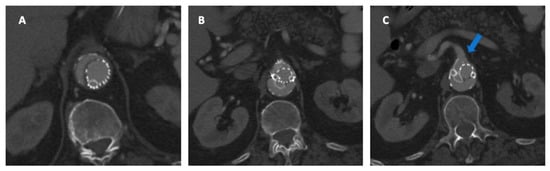

- Gallitto, E.; Faggioli, G.; Vacirca, A.; Pini, R.; Mascoli, C.; Fenelli, C.; Logiacco, A.; Abualhin, M.; Gargiulo, M. The benefit of combined carbon dioxide automated angiography and fusion imaging in preserving perioperative renal function in fenestrated endografting. J. Vasc. Surg. 2020, 72, 1906–1916. [Google Scholar] [CrossRef] [PubMed]